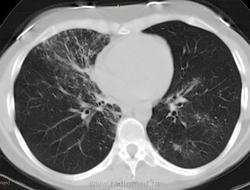

38 лет. 6 лет назад cr носоглотки. Лучевая и химиотерапия. С июля 2012 г. клиника бронхолегочного заболевания.

Флюорография 2010 - норма. В анамнезе хронический гайморит. Бронхоскопия- признаки неспецифического эндобронхита. Исходная флюорография на бумажном носителе с низким качеством изображения. Описаны тени в верхушках легких, воспалительные изменения в средней доле. Лечение макролидами амбулатороно  дало кратковременный эффект.

Узелки хаотичного распределения (туб, микозы, мтс). Участки, напоминающие дерево-в-почках. На верхушках посттуберкулезный фиброз, при этом верхние отделы, насколько можно судить, чистые. Прикорневой фиброз и тракционные бронхоэктазы нижних отделов. Преобладание процесса в нижних долях + фиброзные изменения, +  утолщение??? междолькового интерстиция. Значимой лимфаденопатии не нашла, выпота тоже.

На первое место - неспецифическая интерстициальная пневмония. Спецпневмофиброз верхушек. Насколько возможна реактивация туберкулеза прогнозировать не берусь.

Присоединюсь к ЛГ (со всеми ее оговорками): ДИЗЛ, неспецифическая интерстициальная пневония, участки фиброза, бронхиолита.